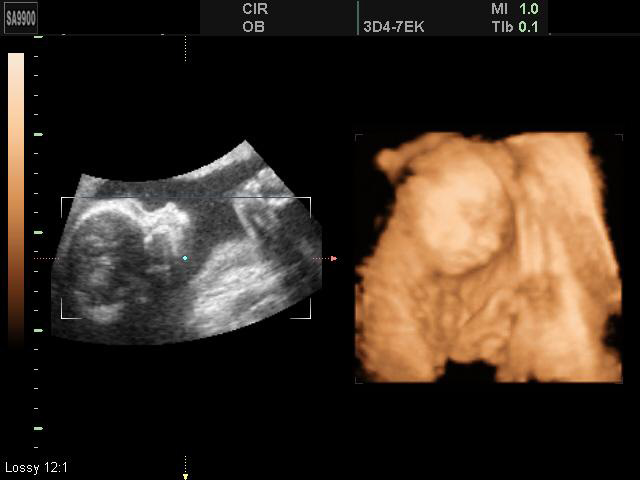

Двойня 3D-УЗИ

27-28 недель